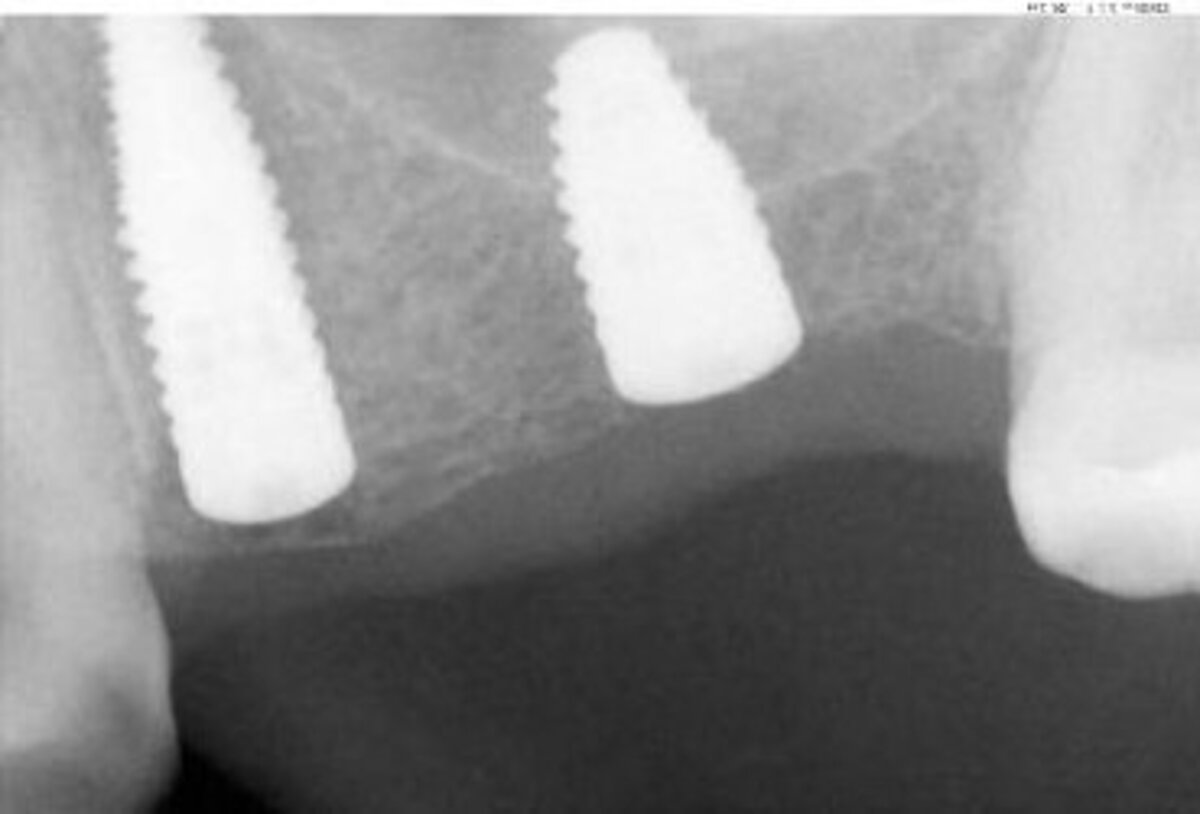

A 73 years old female patient presented after loss of the metal-ceramic bridge in teeth position 24-27, as a result of root vertical at tooth 24. After extraction, tooth 24 and 26 were replaced by bone level implants, while at tooth 24, sinus was simultaneously lifted using crestal approach and Geistlich Bio-Oss® Collagen.